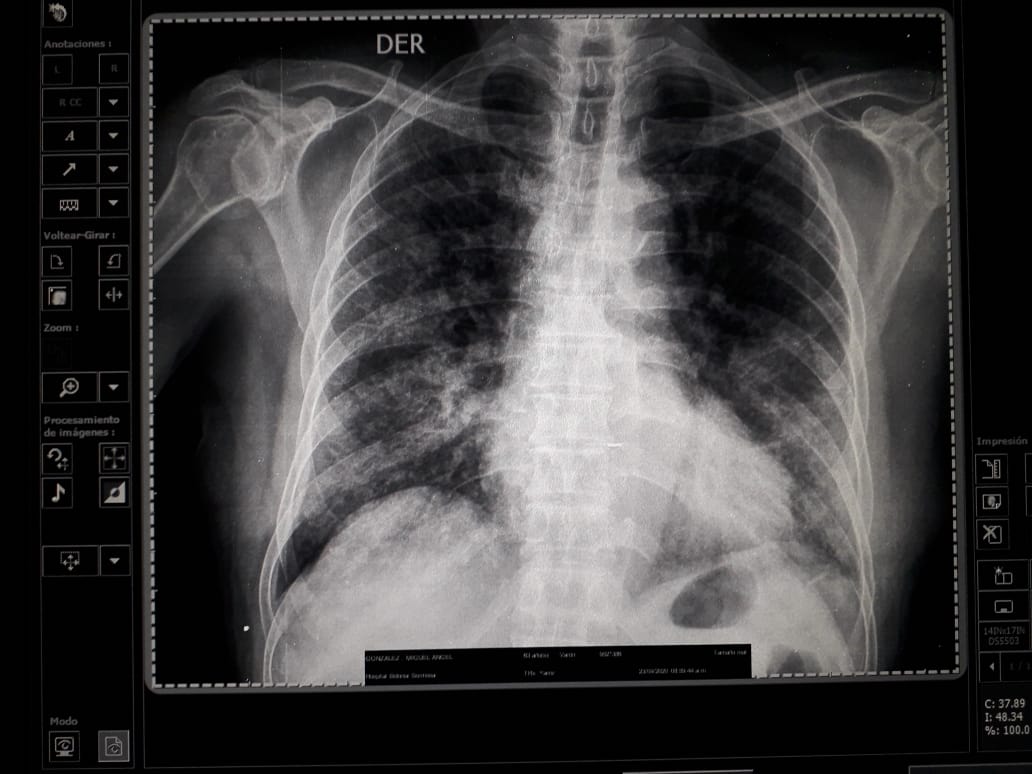

Un mes más tarde, con el pico de contagios en su etapa más álgida, y con la dificultad de matizarlos ante tantos entierros, la vicepresidenta Rosario Murillo admitió un aumento del 54% de muertes por neumonía. Sin embargo, no las asoció al coronavirus. En aquel momento, DIVERGENTES recopiló con fuentes médicas más de cincuenta radiografías de pulmón de diversos hospitales del país, en la que los casos neumónicos eran evidentes. Los doctores aseguraron que no les cabía duda de que se trataban de casos de COVID-19, pero la mordaza impuesta por la autoridad sanitaria y la centralización de las pruebas impedían alertar a los familiares de los contagiados. Médicos sostienen que haber minimizado el impacto de la pandemia, generó más contagios y muertes.